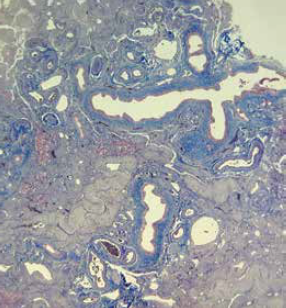

Paciente asintomático, sin alteraciones en los exámenes de laboratorio, por lo que se decidió alta ambulatoria. En la biopsia hepática (figuras 3 y 4) se reportó: hipoplasia hepática, espacios porta conservados con prominencia de los componentes vasculares, hepatocitos con cambios regenerativos y colestasis intracitoplasmática.

Imágenes: Núñez-Venzor et al.

Figura 4 Corte teñido con tricrómico de Masson en donde se hace evidente la fibrosis en los espacios porta